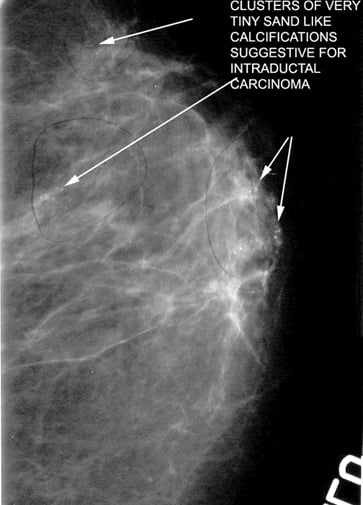

Mikrokalsifikasyonlar: LR (+) 15.0. (Özellikle pleomorfik/dallanan tipteyse)

Luminal A Dominansı: Spiküle (kenarları ışınsal uzantılı) kitlelerin %71'i Luminal A alt tipi olarak sınıflandırılmıştır.

Olasılık Oranı (Odds Ratio): Luminal A alt tipindeki kitlelerin, diğer alt tiplere oranla mamografide spiküle görünüm sergileme olasılığı 10.3 kat daha fazladır (p < 0.001).

Biyobelirteç Korelasyonu: Spiküle görünümün en güçlü öngörücüleri Düşük Ki67 indeksi (< %14) ve HER2 negatifliğidir. Hormon reseptör (ER/PR) pozitifliği de ilişkili bulunmuştur ancak etkisi Ki67 ve HER2 kadar baskın değildir.

Mamografide görülen spiküle kitle, invaziv meme kanserinin Luminal A alt tipi için güçlü bir radyolojik belirteçtir. Bu korelasyonun temelinde tümörün düşük proliferatif aktivitesi (Ki67) ve HER2 gen ekspresyonunun olmaması yatar. Bu veriler, "spiküle kitle" verisinin, biyopsi öncesi Luminal A olasılığını (prior probability) belirgin şekilde yükselttiğini kanıtlamaktadır.